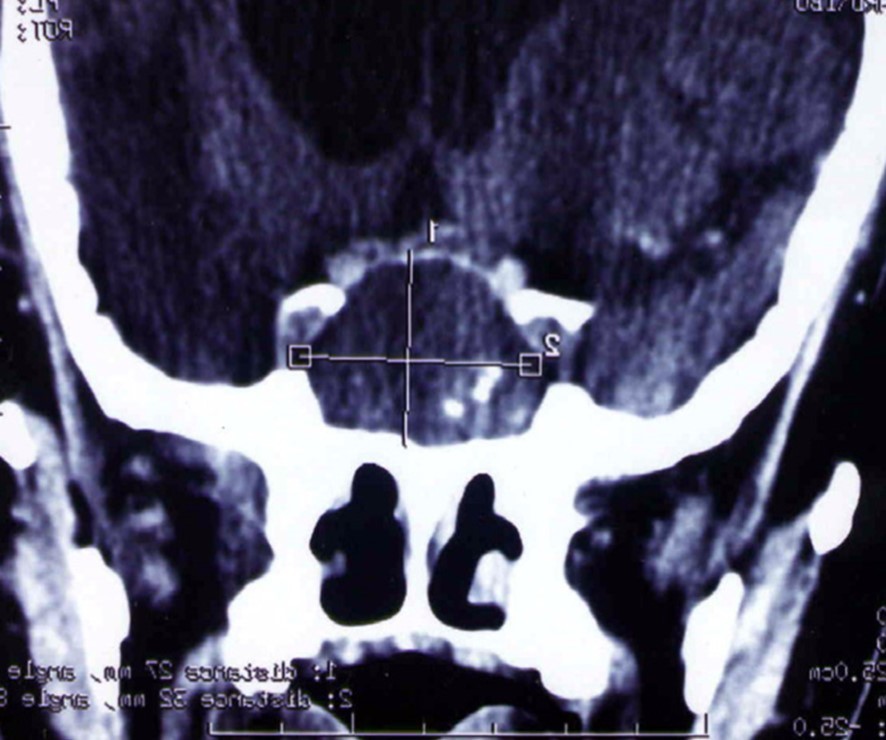

A 65 year-old man presented with progressive visual decrease and ptosis in the left eye. Neurological examination revealed paresis of the 3rd left cranial nerve. Fundoscopy revealed bilateral papillary paleness and visual acuity was: 4/10 at left; 7/10 at right. No signs of endocrine insufficiency or hypersecretion were assessed. There was no evidence of sinusitis. Chest X-ray, routine laboratory investigations and hormonal blood tests were normal. A CT scan showed a hypodense mass enlarging the sphenoid sinus and sellar region with calcification like images and bone erosion of the sellar floor (Figure 5). MRI showed a mass of 26 mm x 33 mm x 25 mm in the sphenoidal sinus ans sellar region, with hypersignal intensity in T1-weighted (Figure 6A) ans T2-weighted sequences, and hyposignal zone in T2-weighted sequences (Figure 6B). Imaging investigations were suggestive of unusual pituitary macroadenoma. The patient underwent a transnasal transsphenoidal approach for excision of the mass. A yellow-brownish gluey material with gummy debris was aspirated from the sphenoid sinus, which was completely cleaned. The sellar floor was eroded which allowed a view of the intact inflammatory dura. An intra-operative presumptive diagnosis was made of caseating granuloma (i.e tuberculosis). The post-operative course was uneventful: the patient recovered from ptosis and visual acuity improve at discharge. Mycobacterium tuberculosis could not be cultured from specimens; and cultures on Sabouraud’s medium did not isolate Aspergillus. Pathologic findings were of non invasive aspergillosis, with many septated fungal hyphae being present without tissue invasion. The patient was not given antifungal drugs because the intrasphenoidal material was completely aspirated. At 6 month and 18 months follow up, the patient had no neurological complaint. No recurrence was observed on control CT scans.

Figure 6.(a) Sagittal T1-weighted MRI showing a well circumscribed hyperintense process in the sphenoidal sinus and sellar region; (b) parasagittal T2-weighted MRI showing a regular hypointense zone into the hyperintense process which is specific to aspergillus infection and corresponds to iron accumulation